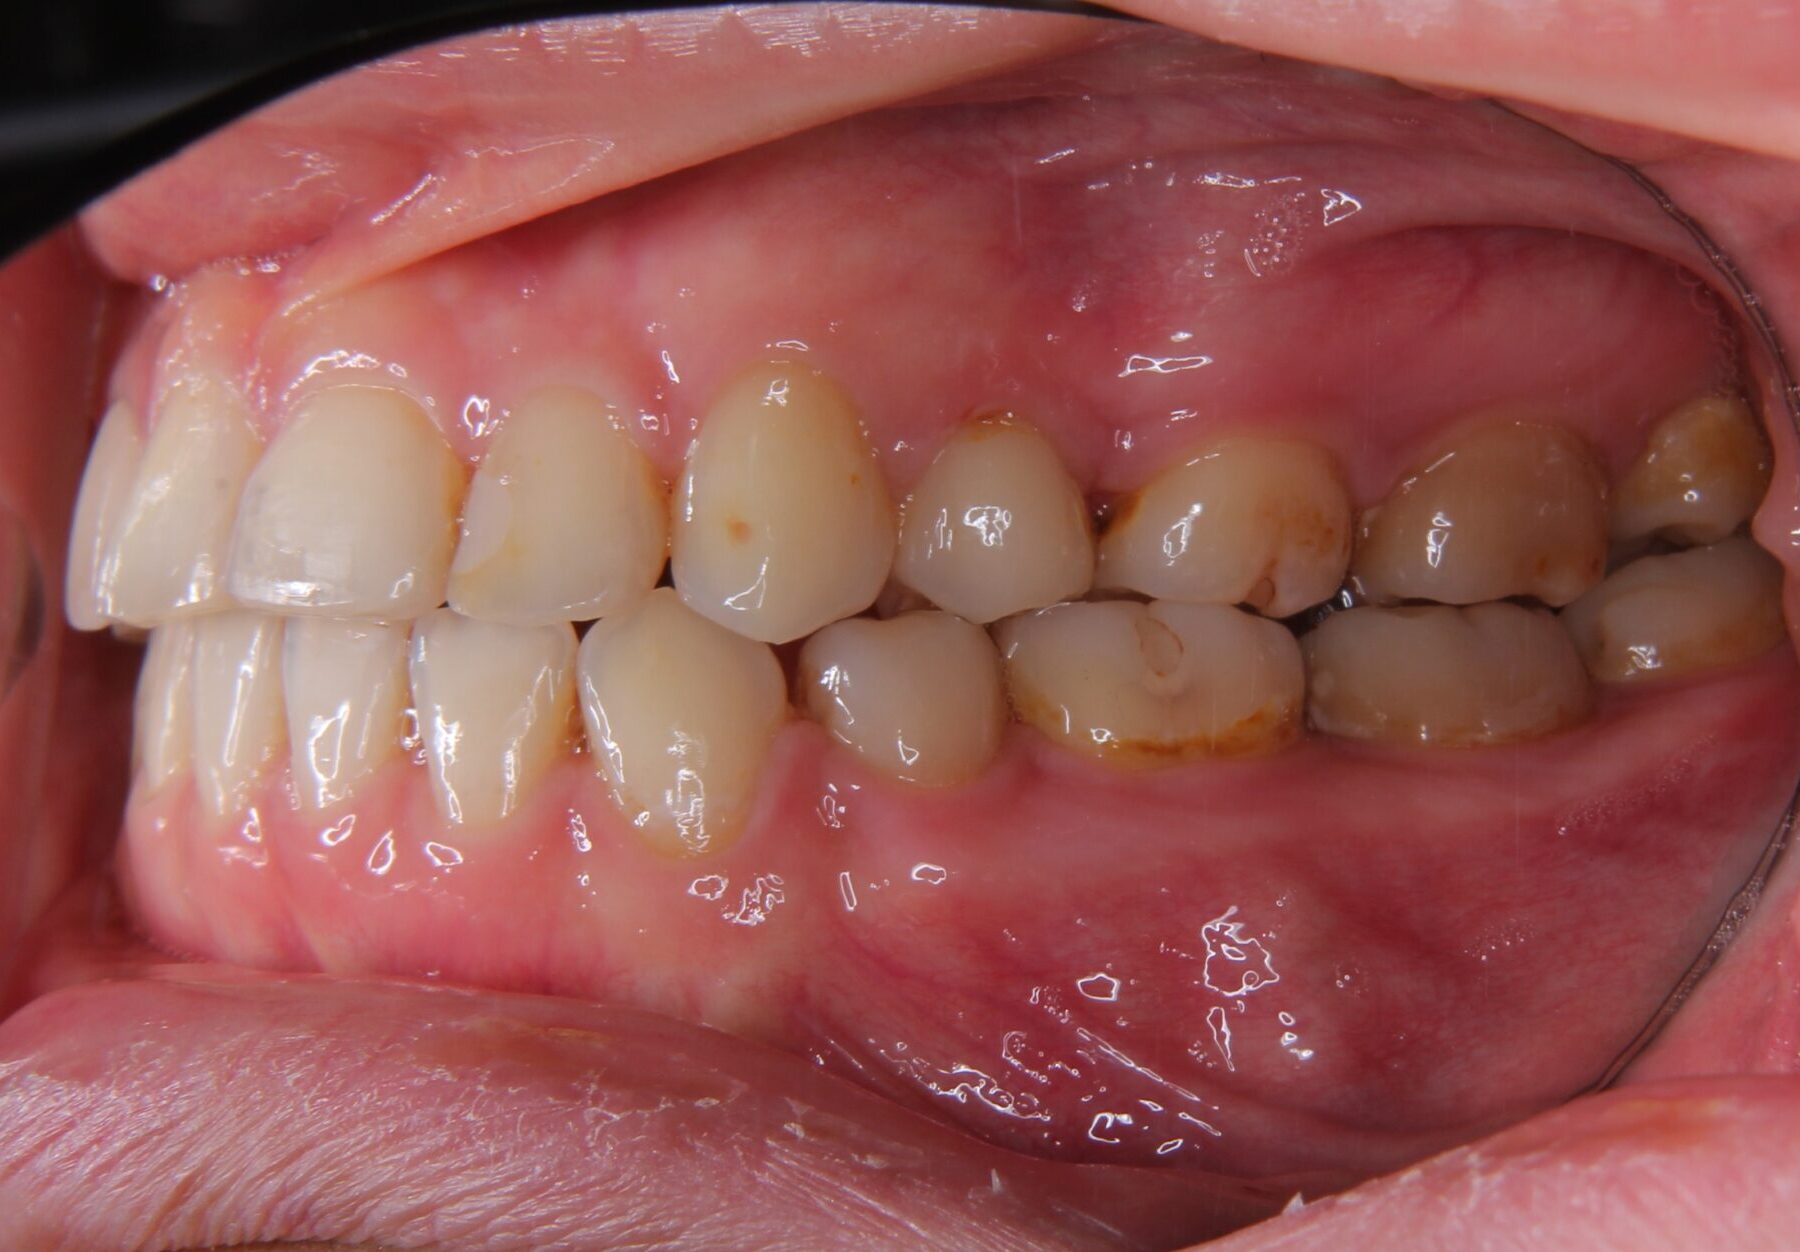

診断名 下顎骨の軽度過成長を伴う上下前歯部叢生症例

年齢 26歳

治療に用いた装置 マルチブラケット装置

抜歯部位 上顎左右5番、下顎左右4番

治療期間 3年(30回)

治療費用 880,000円

リスク・副作用

• マルチブラケット装置装着によるカリエスリスクの上昇